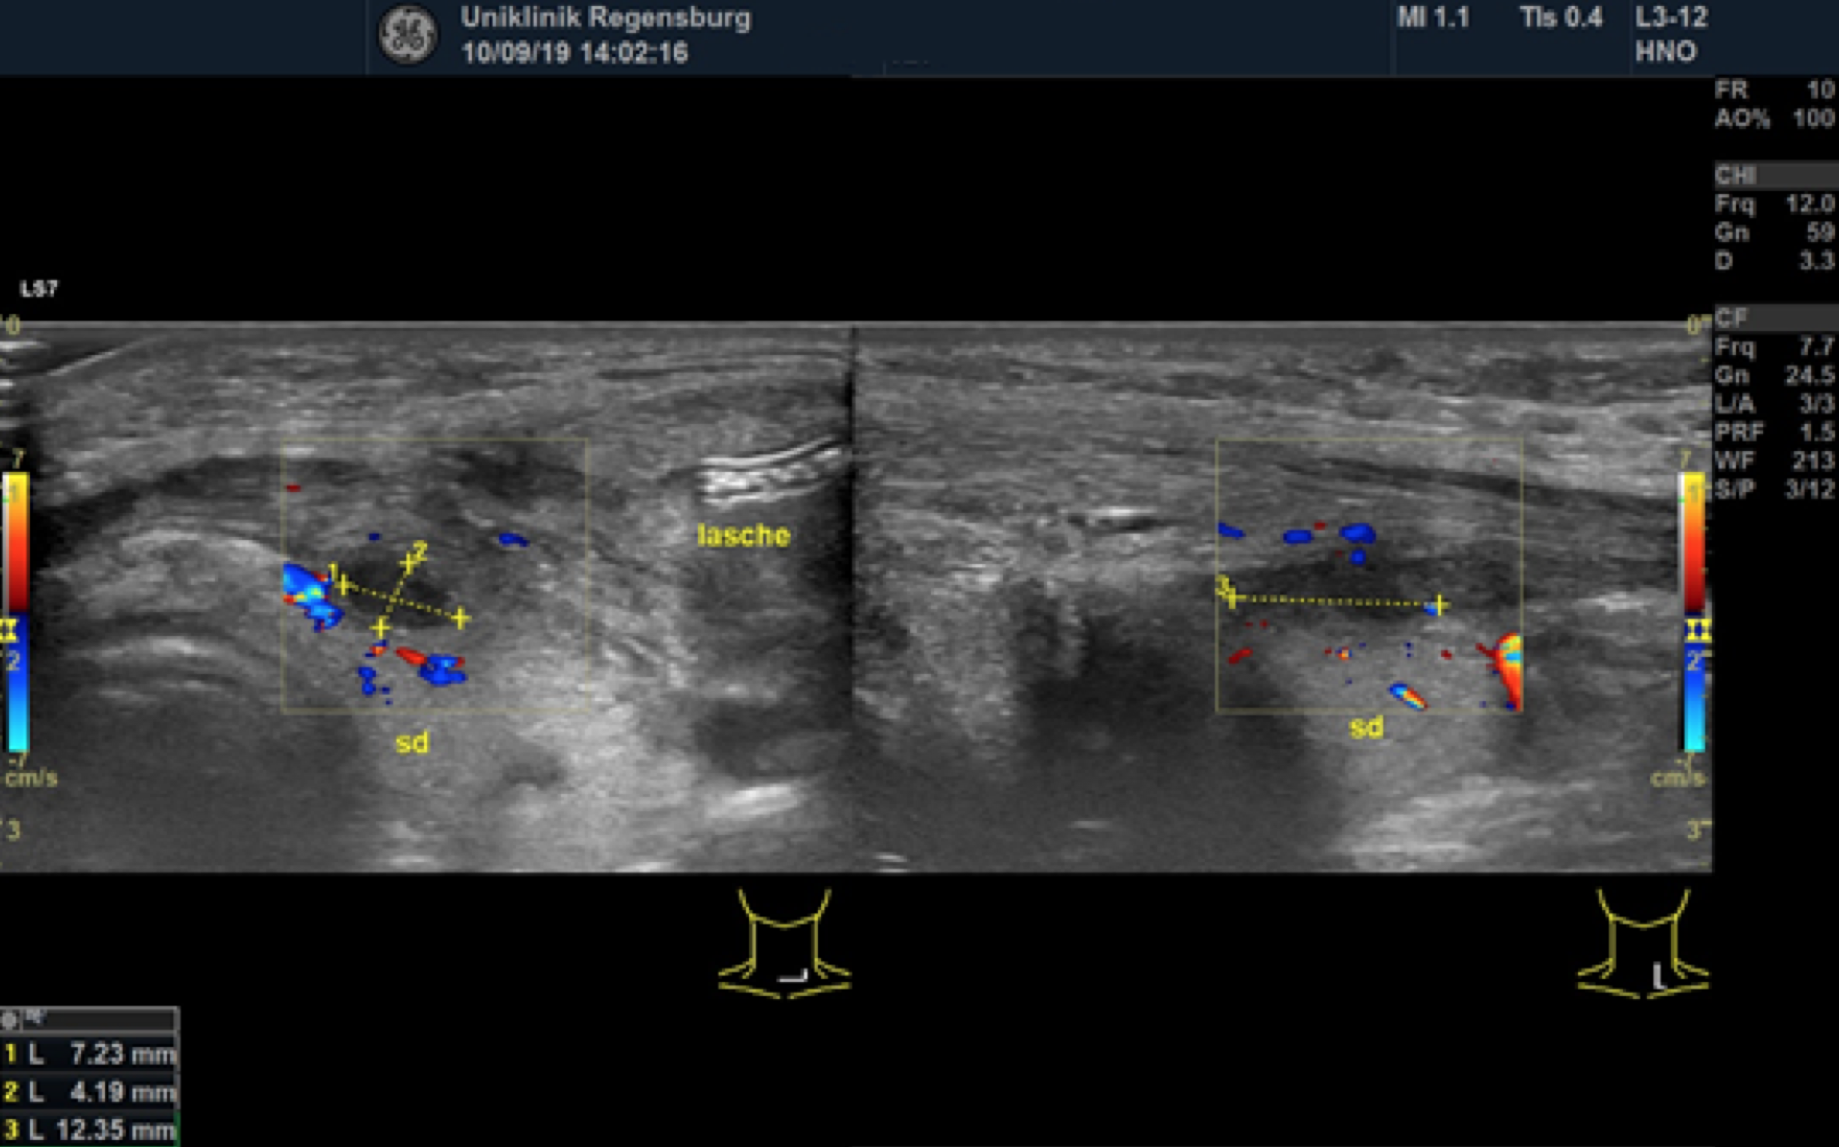

Preoperative ultrasonographic findings showed an oval hypoechoic inhomogeneous mass, approximately 4 x 3 x 1.5 cm in levels III to IV of the left side of the neck below the sternocleidomastoid muscle. (Fig. 1) The mass was partly indistinct to the adjacent tissue and demonstrated peripheral perfusion with no central vascularity. (Fig. 2) The surrounding soft tissues appeared oedematous and thickened. (Fig. 1 – 2)

Sonographic check 2.5 weeks after start of treatment

Figure 7. Status after 2,5 weeks of i.v. antibiotic therapy and drainage. The fluid formation in the left thyroid lobe (sd li) has resolved. The infrahyoid muscle (ihm) and the sternocleidomastoid muscle (mscm) are still mildly thickened. The drain is still in place (lasche in situ). acc = Common carotid artery.